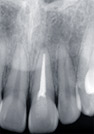

治療前

![]() |

レントゲン像 向かって右の白い部分は神経をとってしっまたからです。 |